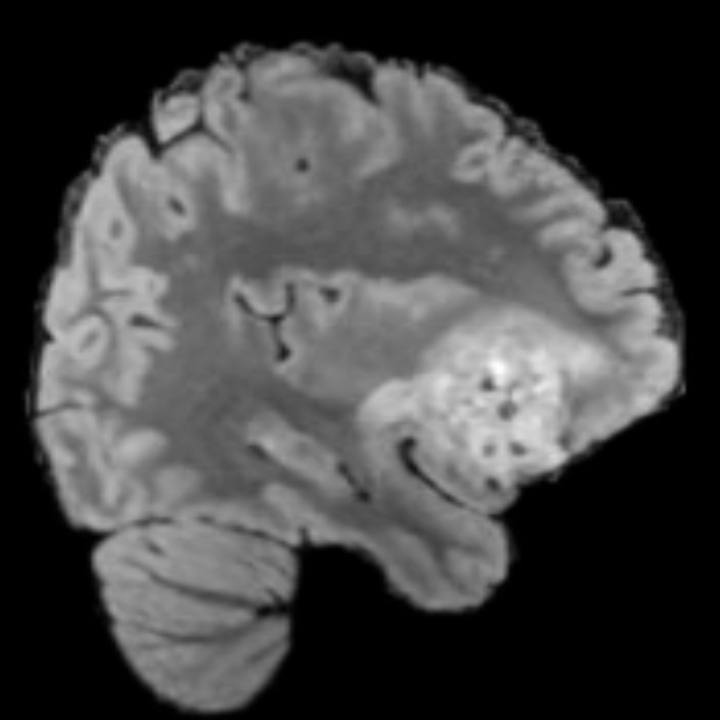

Tumour Information Preservation. For the brain tumor segmentation, we use a Swin UNETR model[28, 70], trained with random rotation, and intensity as data augmentation. On the test set with human ground-truth annotations (), the brain volumes generated from single slice input preserve the volume of the different tumour components (paired t-test, for all 3 classes). In Figure 4, we highlight the tumor profiles of the generated MRIs compared to the ground truth tumour profile. The real MRI Dice score in the test set is 85.15 while the generated MRIs from a single slice have a dice score of 83.09. This shows how the generated MRIs indeed preserve the tumor information and can act as an affordable and informative pseudo-MRI, before conducting an actual costly MRI examination in hospitals. More detailed results are provided in supplementary material.

Leveraging Context. Since we train on a predominantly cancerous brain dataset, one question that might arise is whether X-Diffusion generated MRIs preserve tumour information when the given inputs do not intersect with any tumour. We perform experiments varying the input slice index used to generate the 3D brain MRIs and measure the performance for input slices with no intersection with the tumour (not a single pixel with tumor label in the input slice). We also measure performance when only input slices are selected from tumor range. The Dice Scores of the random slices, no-tumour, and only-tumour are 83.09, 79.23, and 83.68 respectively. As can be seen here, the brain volumes generated from input slices with no tumour still preserve tumour information in reconstructed brain volumes despite a small drop in performance. This indicates that X-Diffusion is leveraging the context to preserve key information, such as tumor locations. This observation is consistent with how tumor segmentation models with global context [13] perform better than local-based U-Nets. More details are provided in supplementary material.